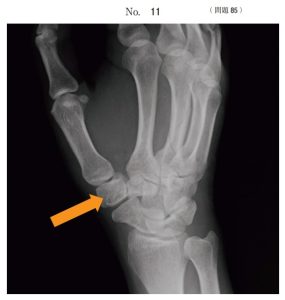

午後/問題85

手の X 線写真(別冊No. 11)を別に示す。

矢印で示す骨はどれか。

1.月状骨

2.舟状骨

3.有鉤骨

4.小菱形骨

5.大菱形骨

答え

5